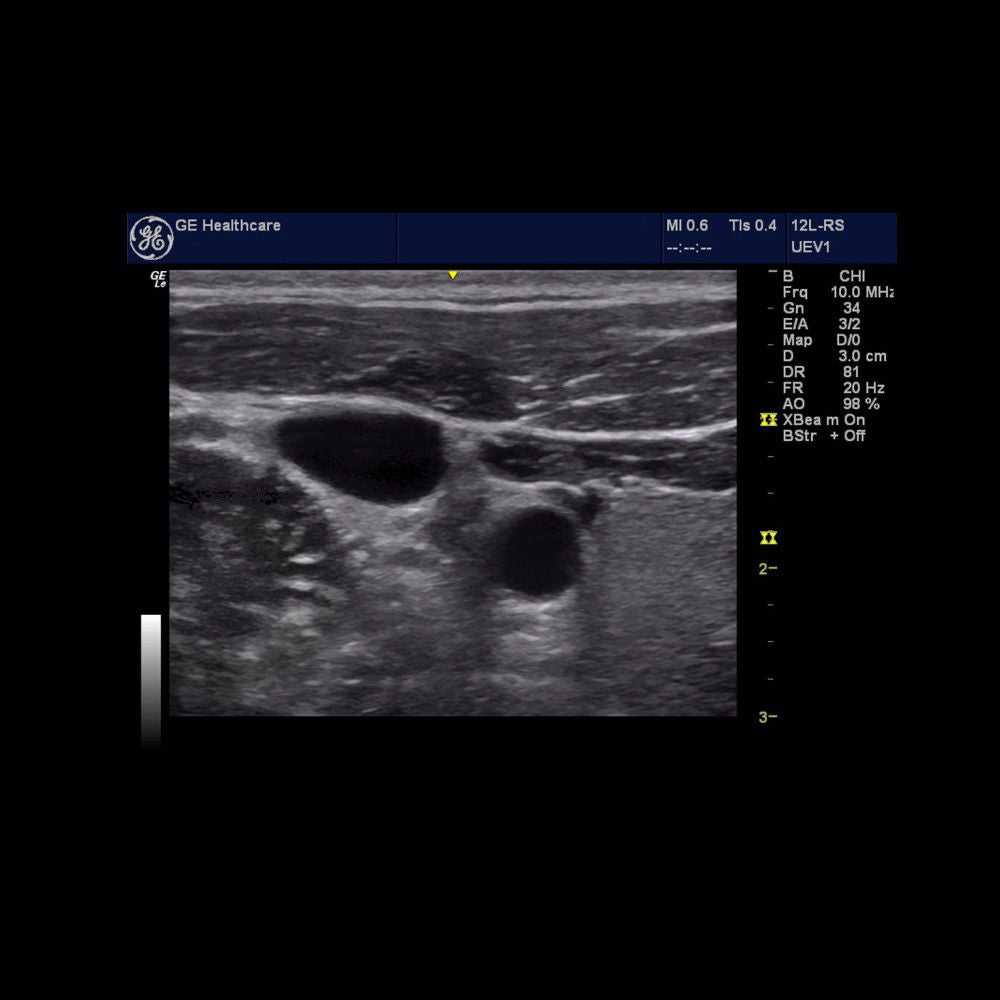

Description

Brand: LOGIQ E

MPN: LOGIQE-FOR-MSK-VASCULAR-LAPTOP-SCANNER-NOTEBOOK